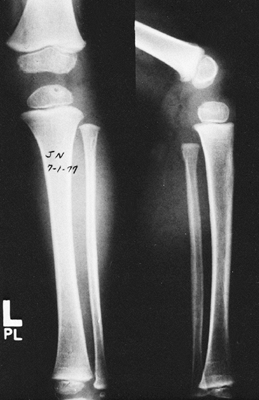

If the lesion is in the epiphysis and a surgical approach is

several weeks (Fig. 176.6). However, most

![]() |

Figure 176.6. Lesion in the proximal epiphysis of the tibia.